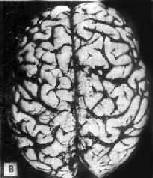

肉眼观,脑萎缩明显,脑回窄、脑沟宽,病变以额叶、顶叶及颞叶最显着(图16-32),脑切面可见代偿性脑室扩张。

图16-32 初老期痴呆的脑

示脑明显萎缩(A),与正常脑(B)的对比